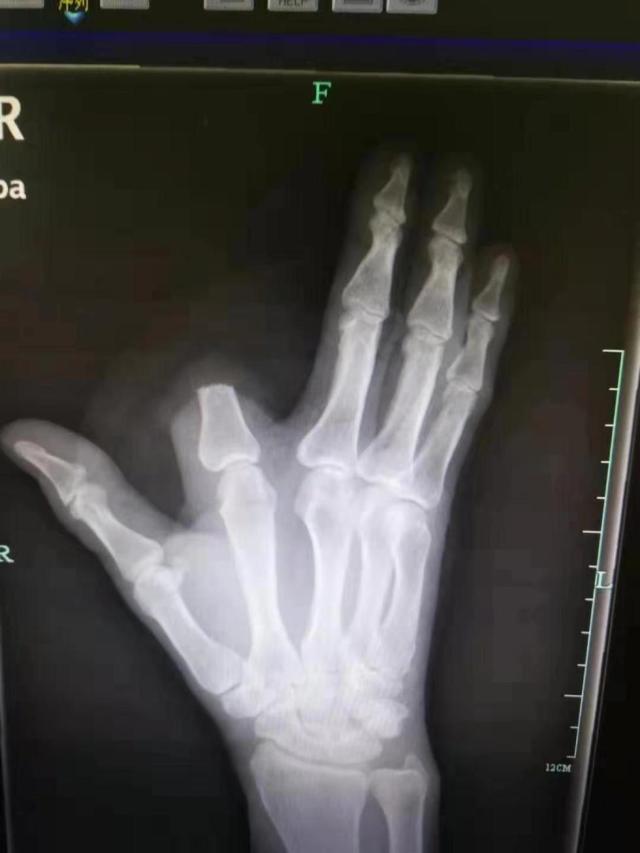

其实单纯从毒性来说,五步蛇的蛇毒并不是很厉害,但是人家的剂量大啊。中国致死率第一的毒蛇不是它,但是说到致残率它可就厉害了,不少人被咬了之后没有及时就医,导致需要进行截肢手术。那么我们被五步蛇咬了该怎么办呢?

如果离医院太远的话,自己也可以做点急救措施,但一定要及时去医院治疗。五步蛇的毒性凶猛,有着形状宛如倒钩的管状毒牙,不仅长,而且大。也正是因此,它可以注射大剂量的毒液到猎物体内,确保猎物的死亡,被它咬伤的伤口也一般也比较严重。

被五步蛇咬了之后,大家一定要镇定,不要自己吓自己,大部分情况下及时就医是可以治好的,不要心一狠,直接自己就给自己截肢了,那样后悔就来不及了。杭州一男子张先生在山上干活时被毒蛇咬伤了,在发现是五步蛇之后,他居然直接拿刀砍掉了自己一部分的食指,也是个狠人啊。